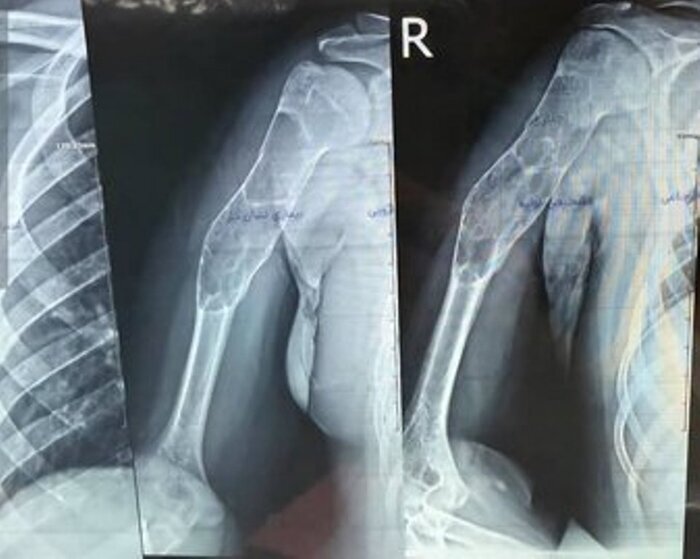

پیوند موفقیت‌آمیز استخوان مصنوعی بازو در پارس‌آباد

عمل جراحی پیوند استخوان مصنوعی بازو به یک بیمار پسر ۱۶ ساله در پارس‌آباد مغان با موفقیت انجام شد.

به گزارش خبرگزاری صداوسیما، مرکز اردبیل مدیر شبکه بهداشت و درمان پارس‌آباد  گفت: این عمل جراحی به رغم وجود توده کیستیک وسیع در بازوی این نوجوان،  توسط دکتر شهریار خوشبخت جراح و متخصص ارتوپدی و با همکاری تیم جراحی بیمارستان امام پارس‌آباد صورت گرفت.

دکتر شهریار خوشبخت، جراح و متخصص ارتوپدی هم درباره این عمل جراحی گفت: با توجه به وجود توده کیستیک وسیع در بازوی بیمار، تیم جراحی توانست به مدت سه ساعت پس از عملیات پلاک‌گذاری، توده وسیع را تخلیه و استخوان مصنوعی را جایگزین کند.

وی افزود: چنین اعمال پیچیده‌ای به طور معمول توسط فوق تخصص‌های جراحی دست در مراکز استان‌ها انجام می‌شود و خوشبختانه توانستیم برای اولین بار در شمال استان اردبیل در بیمارستان امام (ره) پارس‌آباد این عمل را با موفقیت انجام دهیم و اکنون بیمار با حال عمومی خوب بستری است و پس از چند روز مرخص خواهد شد.